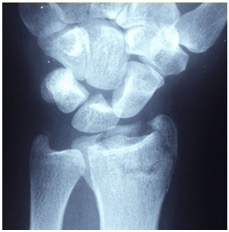

The wrist, one of the most intricate joints of the human body, consists of eight carpal bones, linked by a dense web of ligaments and connected to the radius, ulna (forearm bones), and metacarpals (the five hand bones).

Figure 1. Anatomy of the Human Wrist

Source: Anatomy, Shoulder and Upper Limb, Wrist Joint (Ervin et al. 2023).

This complexity gives us incredible flexibility and control - think everything from setting a ball to gripping a pen - but it also makes the joint prone to instability. A review published in Journal of Orthopaedic Surgery and Research suggests that nearly one-quarter of all sports-related injuries involve the wrist or hand, while repetitive wrist flexion and axial impact - common in volleyball - can greatly increase the risk of tendinopathy and other wrist pathologies (Avery et al. 2016).